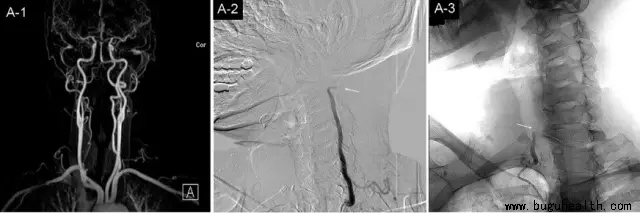

图A-1:为MRA显示双侧椎动脉畅通;

图A-2:显示向右侧转头时左侧椎动脉于C1-2水平受压闭塞;

图A-3:显示向右侧转头时右侧椎动脉于C6水平受压闭塞。